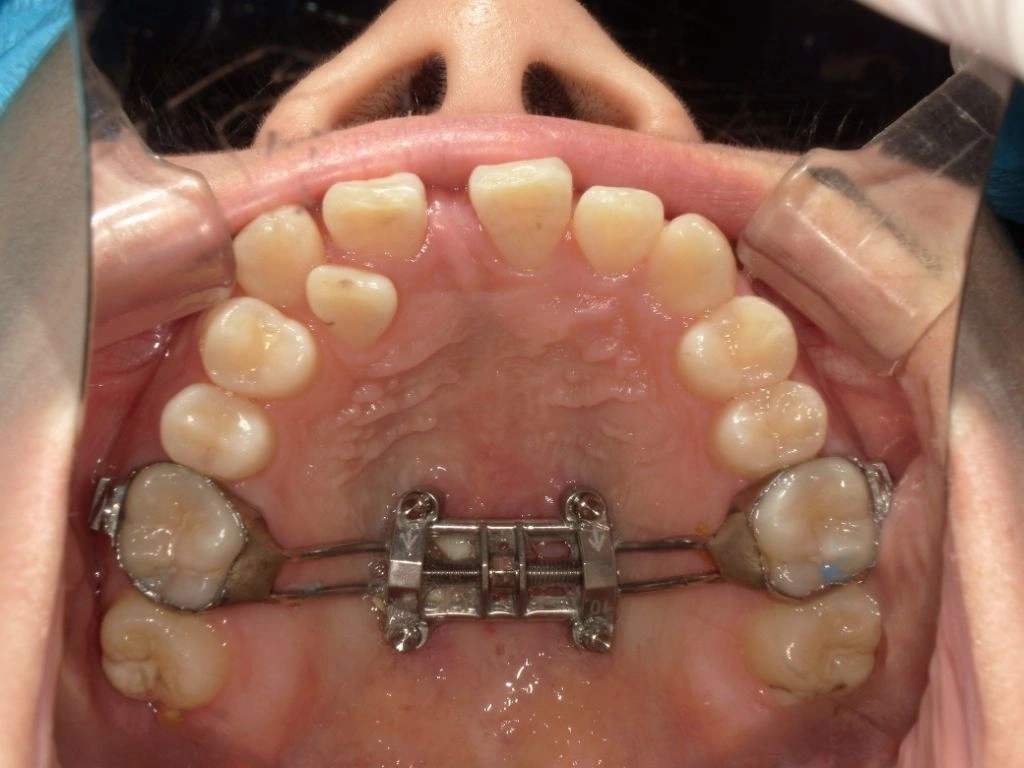

まず、MSEの中央部に正中口蓋縫合をまたぐ位置に4本の矯正用アンカーを埋入しました。浸潤麻酔で痛みなく、15分程度で処置自体は終了です。

中央部にネジを回す部分があるため、付属するレンチを患者さんに1日1回を目安に回していただきます。

初めは拡げる応力が集中するため、鈍痛を感じることもありますが、日常生活に大きな支障が出るほどではありません。

MSEの効果が出てくると、上顎の前歯部には隙間ができます。これは見た目としては我慢ポイントにはなるのですが、確実に正中口蓋縫合が離開して骨格的な拡大ができている証拠でもあるので不安になる必要はありません。

MSEを装着した状態でワイヤー矯正をスタートさせます。オープンコイルを使用しながらスペースを確保しつつ、口蓋側に転位している2番の側切歯を移動させていきます。